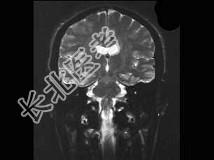

- 单项选择题男,32岁, 头痛、抽搐3年余,MRI检查如图, 最可能的诊断是 ( )

A、先天发育不全

B、灰质异位

C、正常颅脑

D、片状脑梗死

E、脑水肿